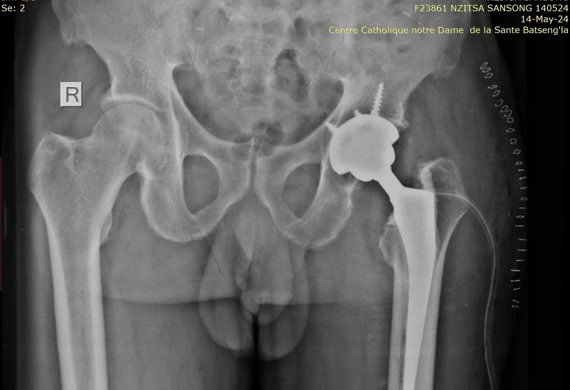

Coste del material de Osteósíntesis para una fractura de fémur

El coste de una intervención quirúrgica de alta complejidad